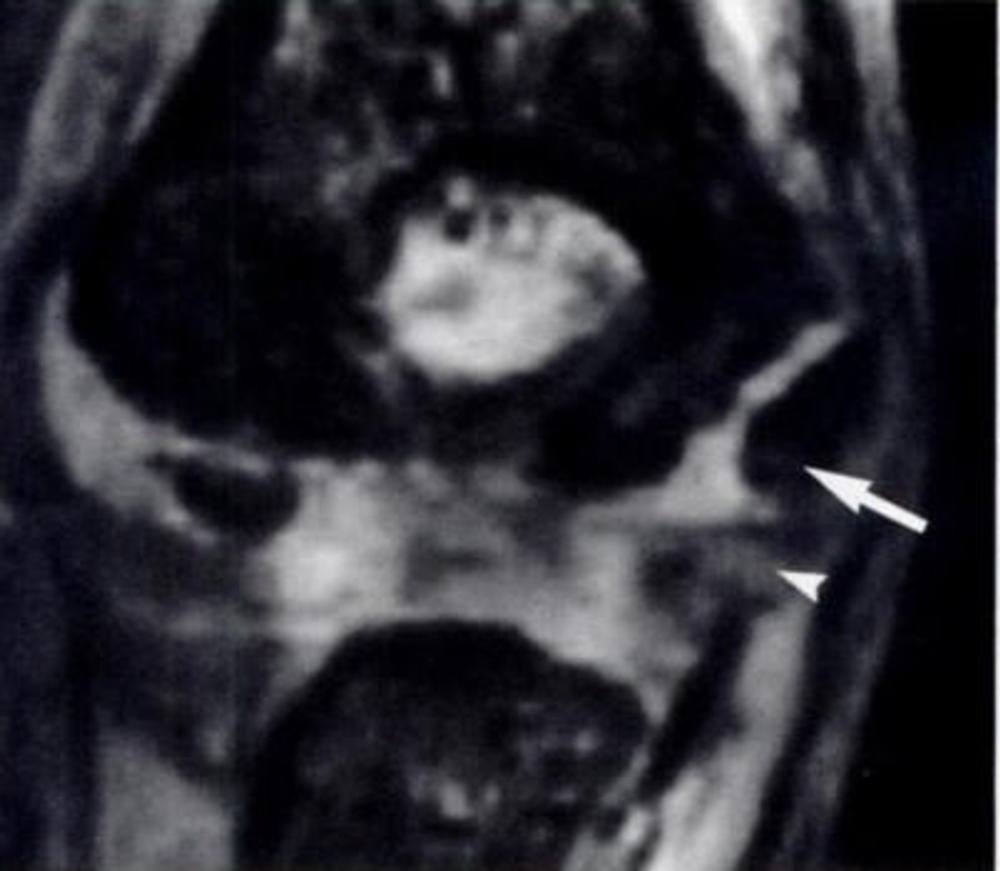

Figure 2. Elbow injury in 12-year-old boy. (Courtesy of Radiology)

Figure 4. MRI findings in elbow among pediatric baseball players and with respect to regional skeletal maturity.